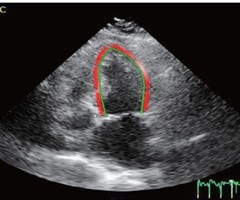

右房容积及心肌应变参数评估中重度功能性三尖瓣反流患者右房功能的临床价值

摘要目的探讨右房容积及心肌应变参数在评估中重度功能性三尖瓣反流(FTR)患者右房功能中的临床价值。方法选取我院经超声诊断的中重度FTR患者60例,其中中度30例(中度FTR组),重度30例(重度FTR组),另选轻度FTR患者14例和同期健康...